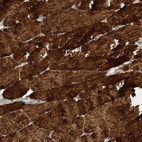

Immunohistochemical staining of human prostate shows moderate cytoplasmic positivity in smooth muscle cells.